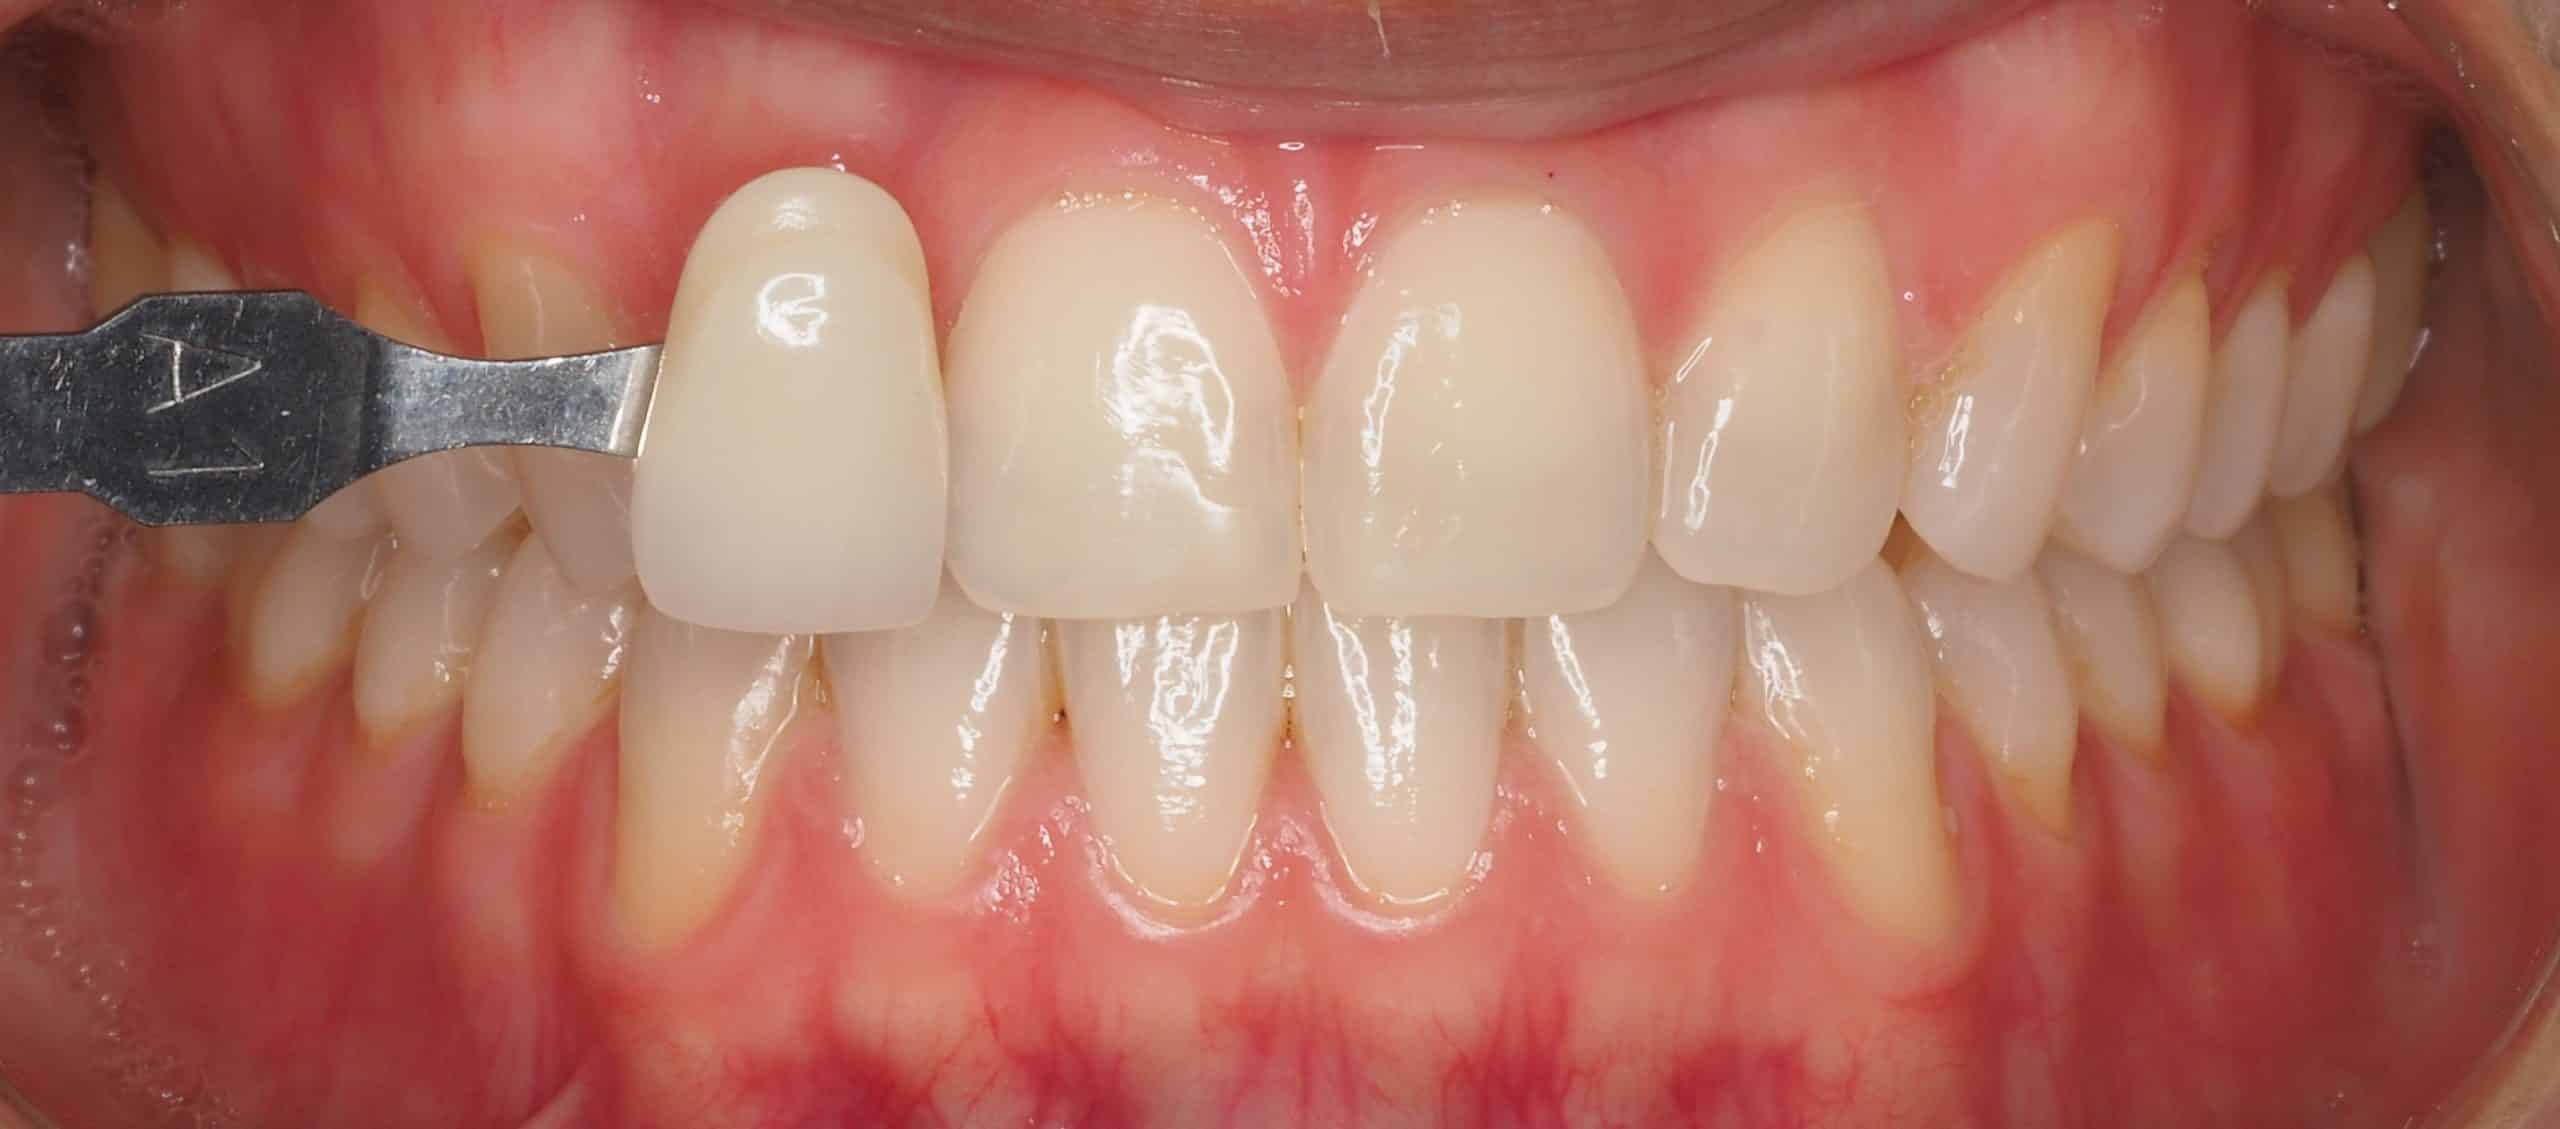

Caso 2

Paciente con dientes desgastados y oscurecidos, se realiza blanqueamiento zoom en una sola sesión.